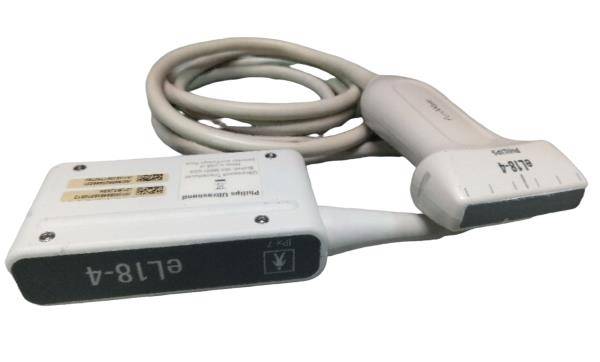

Probe Function: 3.5MHZ convex, abdominal organs

Probe 2: 7.5MHZ Transvaginal probe:gynecologic examination

The Diagnostic Ultrasound Scanner utilizes state-of-the-art B Mode technology to produce high-quality images. This feature allows healthcare professionals to visualize internal structures clearly, aiding in accurate diagnoses. Because it combines both convex and transvaginal probes, the scanner is versatile and suitable for various examinations, making it ideal for hospitals and clinics alike.